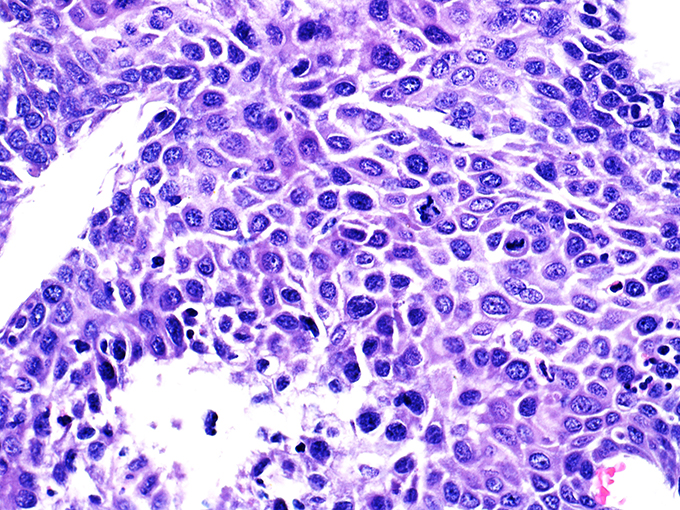

Case 1

Area 1 - Soft Bx CIN 2

40x - High Power